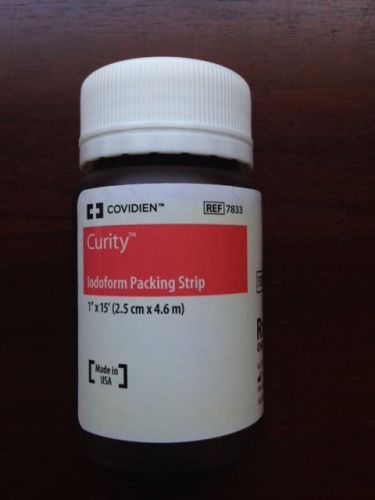

Covidien Curity Iodoform Gauze Packing strips 1"x15' #7833 Sterile